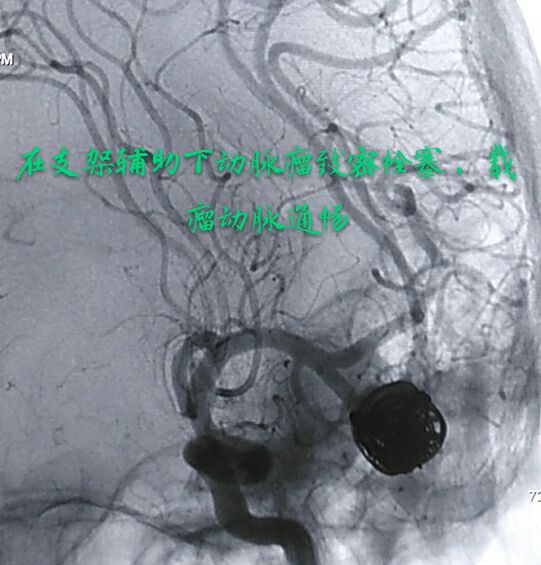

病例四:80岁男性患者,主症:头痛、脑鸣2年,DSA示左侧大脑中动脉下干大动脉瘤,绝对宽颈,载瘤动脉累及程度重

因栓塞难度大,术前做了详细、精准的计划

最准致密栓塞动脉瘤,载瘤动脉完美塑型并受到保护,难点:瘤颈极宽,辅助支架导管通过动脉瘤到达远端困难,最准微导管塑型成大弯,微导丝成袢通过动脉瘤到达远端,成功释放支架,动脉瘤栓塞后患者头痛、脑鸣症状消失